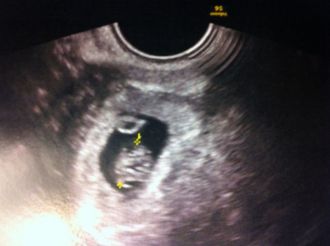

il met enfin la sonde et la une grosse poche mais une activité cardiaque detecté il a du mal a dire si c le sac vitellin uniquement qu'on voit ou un deuxeime mais ne detecte qu'une seul activité cardiaque je reconnais que pour mes autres bébé au meme stade le sac vitellin etait pas comme ça m'enfin chaque bébé est différent ;)

conclusion a ce stade je dirais que UN seul bébé mais a verifier quand meme a l'echo morpho vous serez fixé car il arrive que y'est des surprise

voila les filles l'echo :) et OUI je suis bel et bien qu'a 5 semaine de grossesse + 3 jour environ !